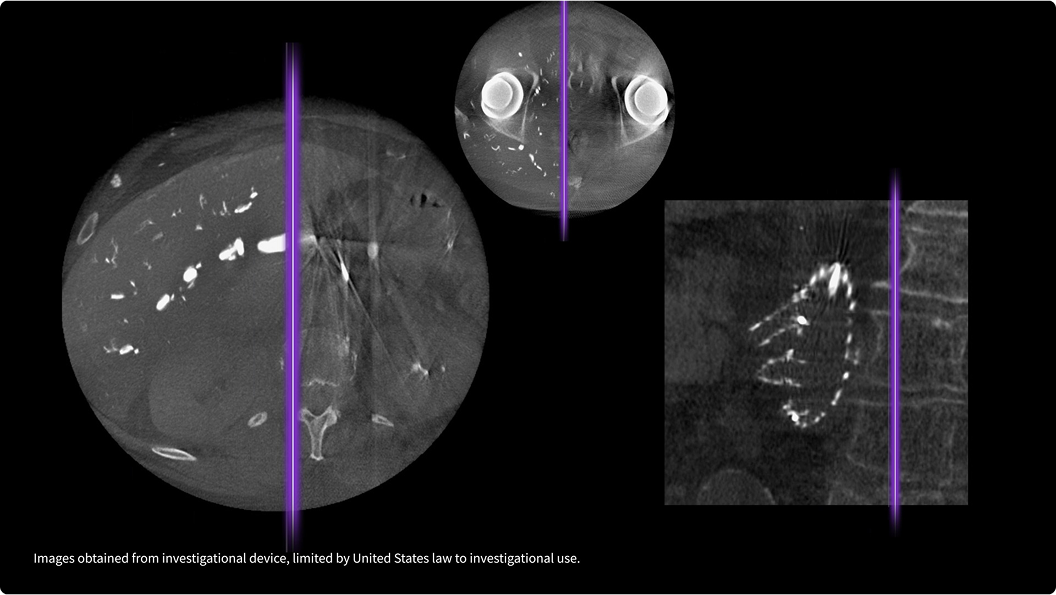

MotionFree esegue il monitoraggio attivo del pattern respiratorio del paziente utilizzando le informazioni provenienti dal flusso di coincidenza PET.

Prende decisioni informate in tempo reale

Grazie all'uso di dati interni, MotionFree è in grado di rilevare automaticamente gli effetti del movimento respiratorio e di decidere in tempo reale se estendere la durata della scansione.

Ogni correzione viene implementata con precisione

Al termine di una scansione, MotionFree elimina gli artefatti da movimento dalle immagini PET. Integra tutte le correzioni del movimento respiratorio nella ricostruzione finale dell'immagine.